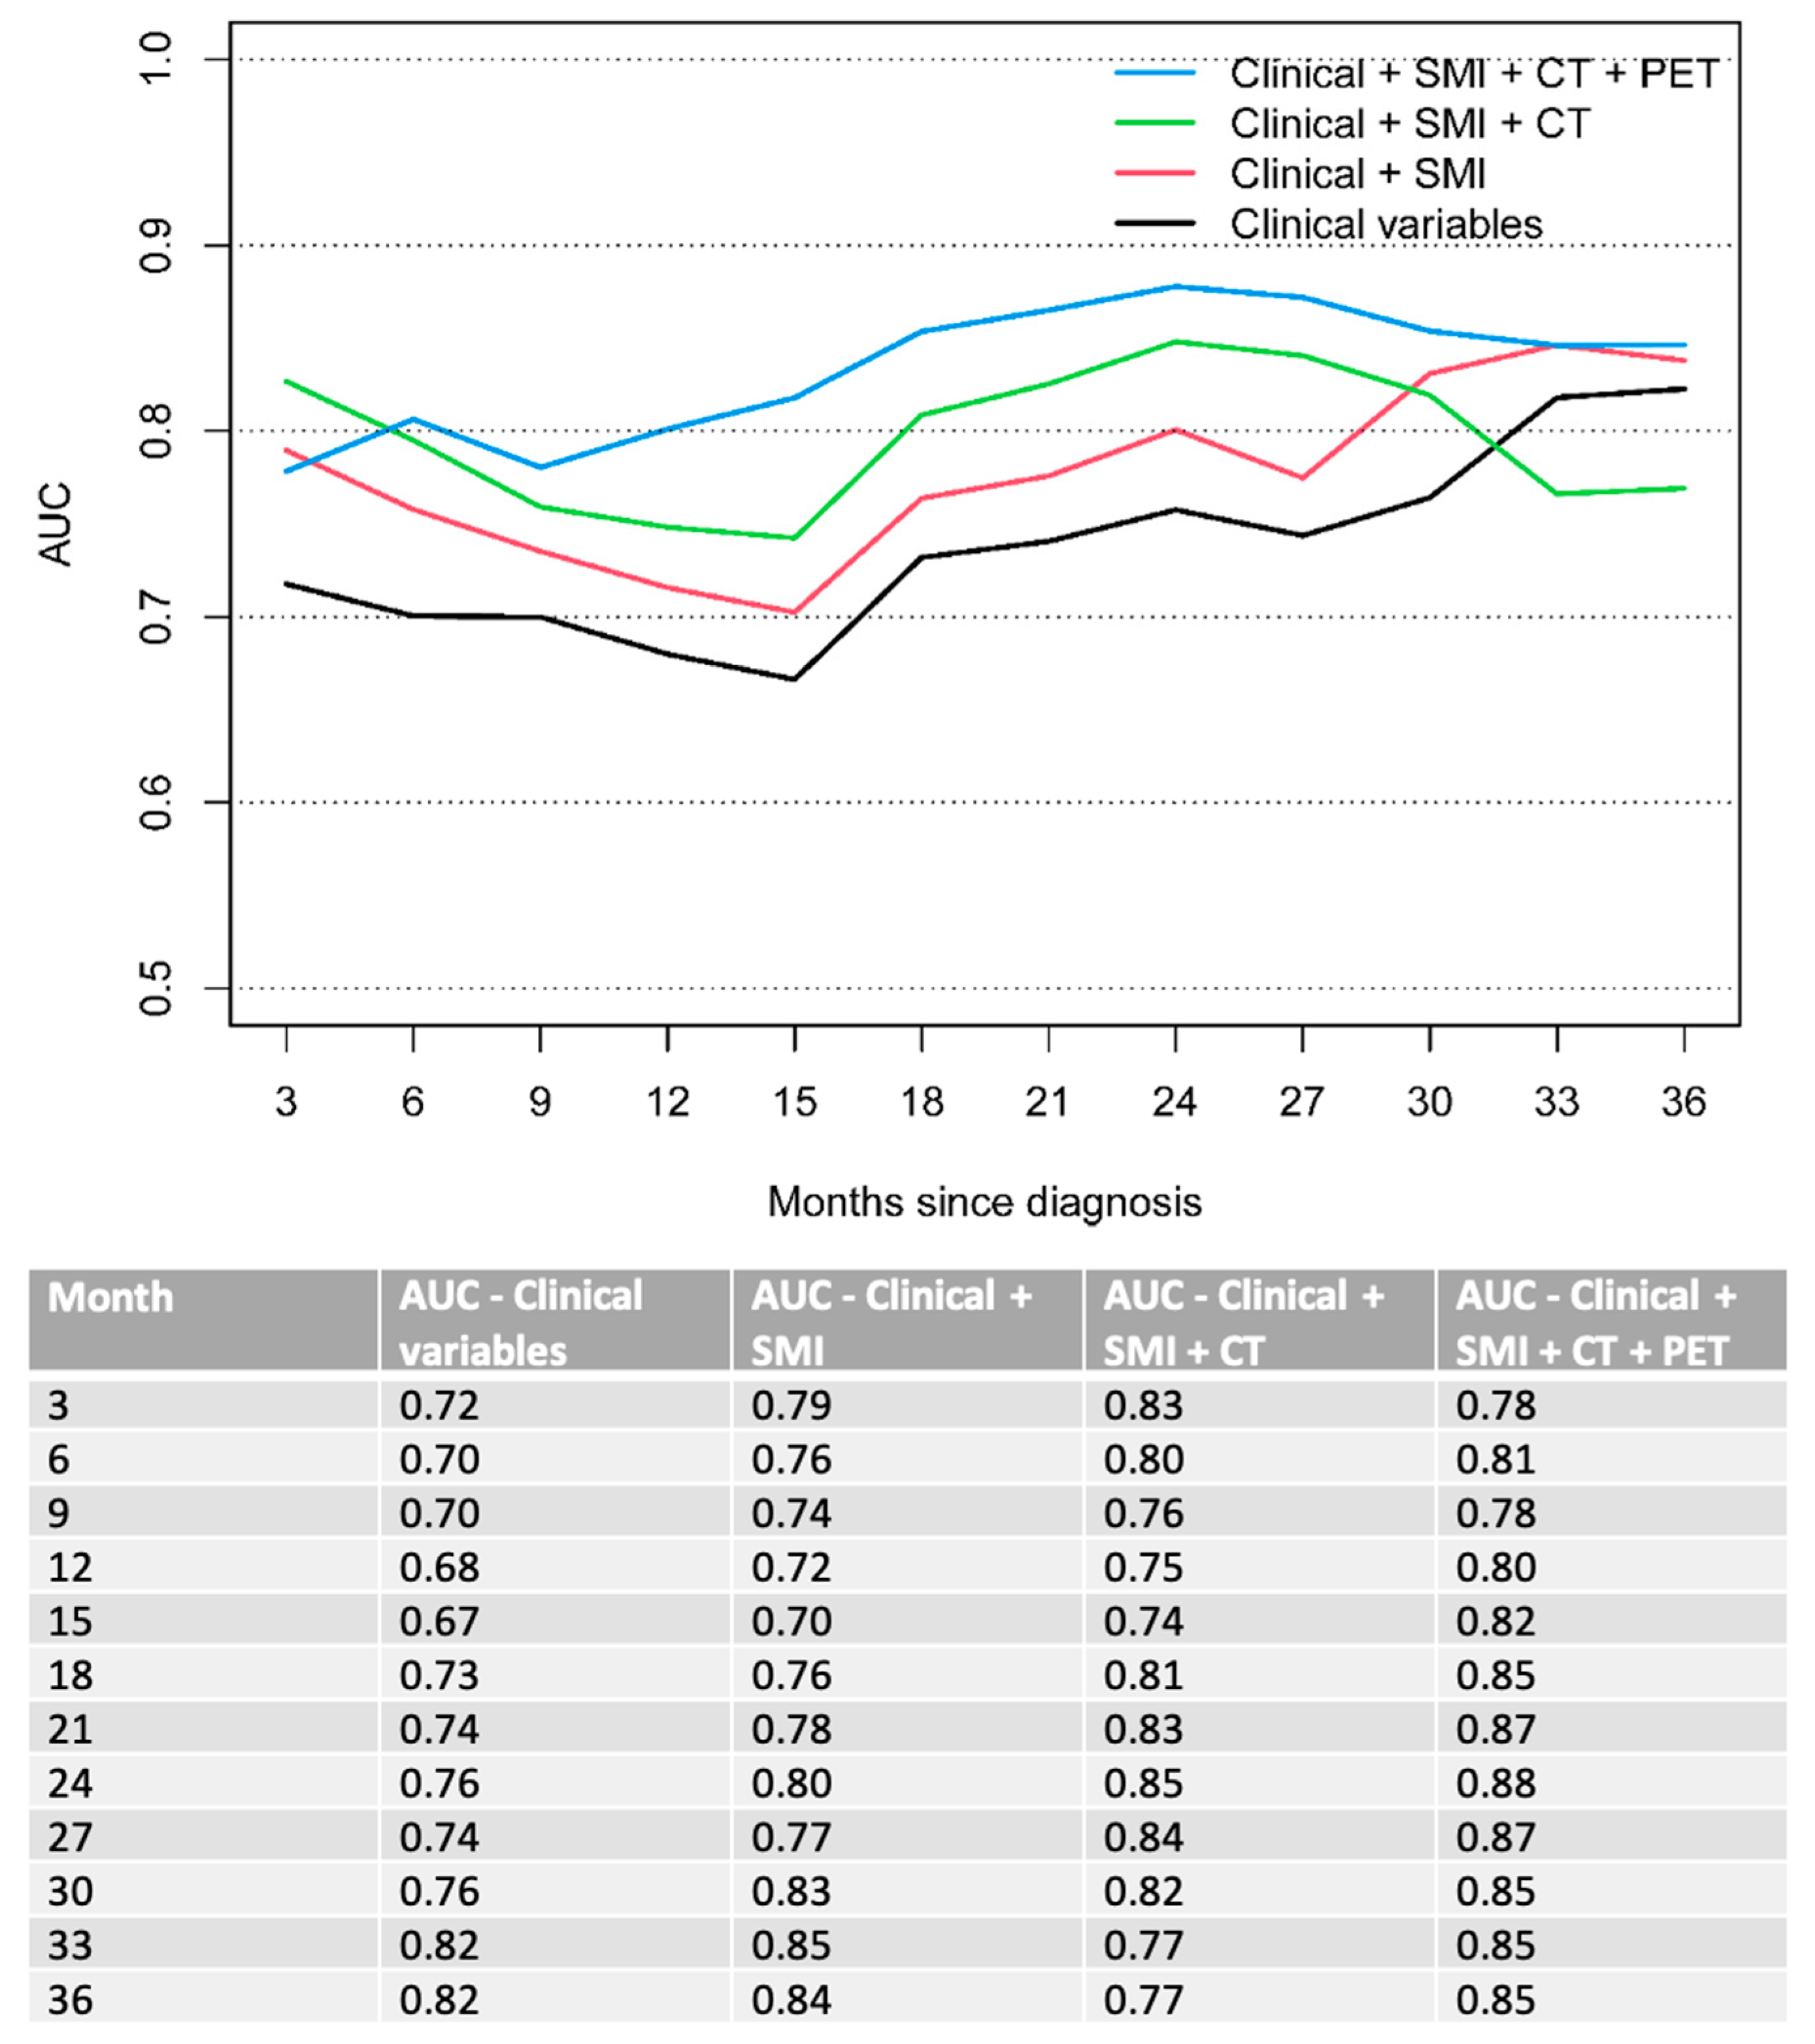

3.2. Multivariable Analysis